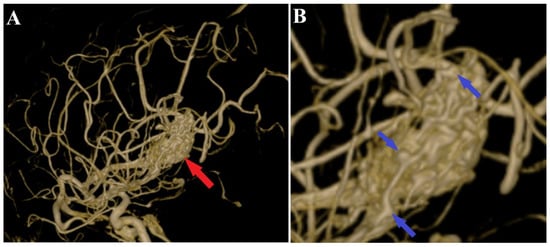

Figure 3.

Preoperative 3D DSA rotational angiography. The 3D reconstruction of rotational DSA (A) depicts the tridimensional topography of the arteriovenous malformation (red arrows). In high-resolution image (B), multiple intranidal sacullar and fusiform aneurysms were found (blue arrows).

A 44-year-old patient was admitted to our clinic for sudden left hemiparesis MRC 1/5 occurring in the apparent health status 48 h prior to admission, followed by the deterioration of consciousness that become gradually worse, with the patient becoming comatose. She was admitted to our clinic with GCS = 7 points (eye response—2 points, verbal response—2 points, motor response—3 points), orotracheally intubated, and mechanically ventilated. Neurological examination on admission revealed a left hemiparesis, predominantly in the brachial region and comatose state. A brain non-contrast CT scan revealed a voluminous right fronto-temporal intraparenchymal hematoma with panventricular infiltration, significant mass effect on the right lateral ventricle, and 1.5 cm displacement of the midline. Otherwise, normal cerebroventricular CT appearance was seen (Figure 1). Angiography was performed through the selective injection of the internal carotid artery bilaterally, right external carotid artery, and left vertebral artery. Right temporal arteriovenous malformation with arterial afferents from the right anterior choroidal artery and right-sided middle cerebral artery was observed, Spetzler Martin grade III (Figure 2). A nidus of approximately 2/1 cm in size with several intranidal aneurysms was also observed (Figure 3). A single vein was draining into the right cavernous sinus, through an intermediate venous source.